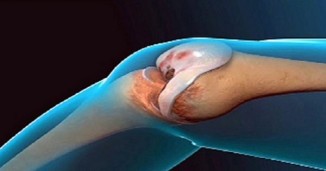

თუ სახსრების ტკივილი გაწუხებთ, ამ საშუალების დახმარებით მასზე სამუდამოდ დაივიწყებთ!

სახსრების ტკივილი შეიძლება დაავადებების: ოსტეოართრიტი, რევმატოიდული ართრიტი, ბურსიტი და პოდაგრას მიზეზით იყოს გამოწვეული. ეს შეიძლება ასევე იყოს..